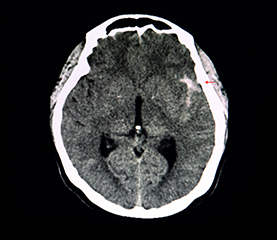

CT Cerebral

Computerul tomograf permite obtinerea unor imagini cu rezolutie crescuta la nivel cerebral. Pentru o mai buna diferentiere a structurilor anatomice se poate administra substanta de contrast intravenoasa.